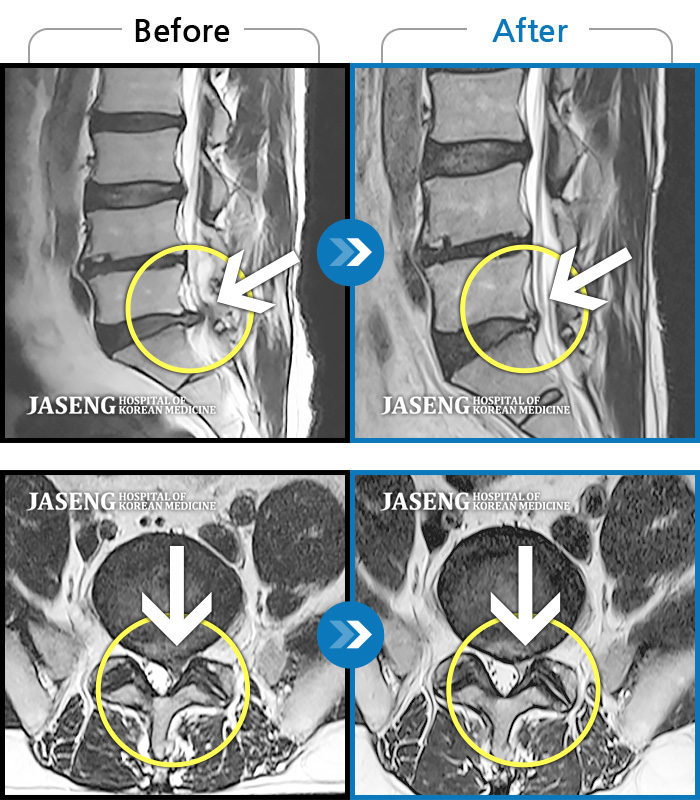

허리디스크

광주 · 김동은 원장

좌측 골반 및 종아리부터 발까지 이어지는 저림과 통증으로 내원하셨습니다.

촬영시기

2023.10.03 ~ 2025.08.14

2025.08.22